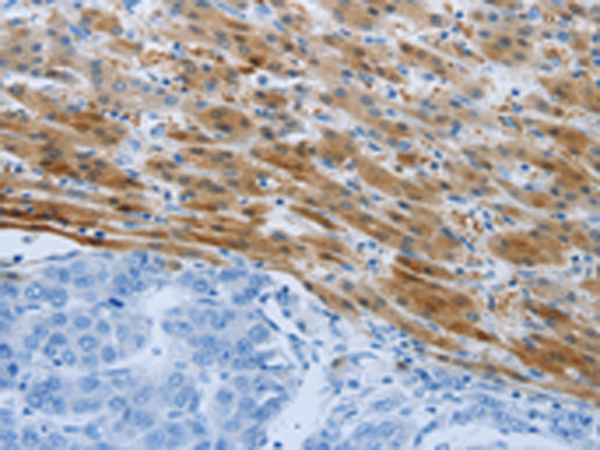

分类: 科研抗体货号: P04438别名: ROS; MCF3; c-ros-1应用: IHC反应种属: Human